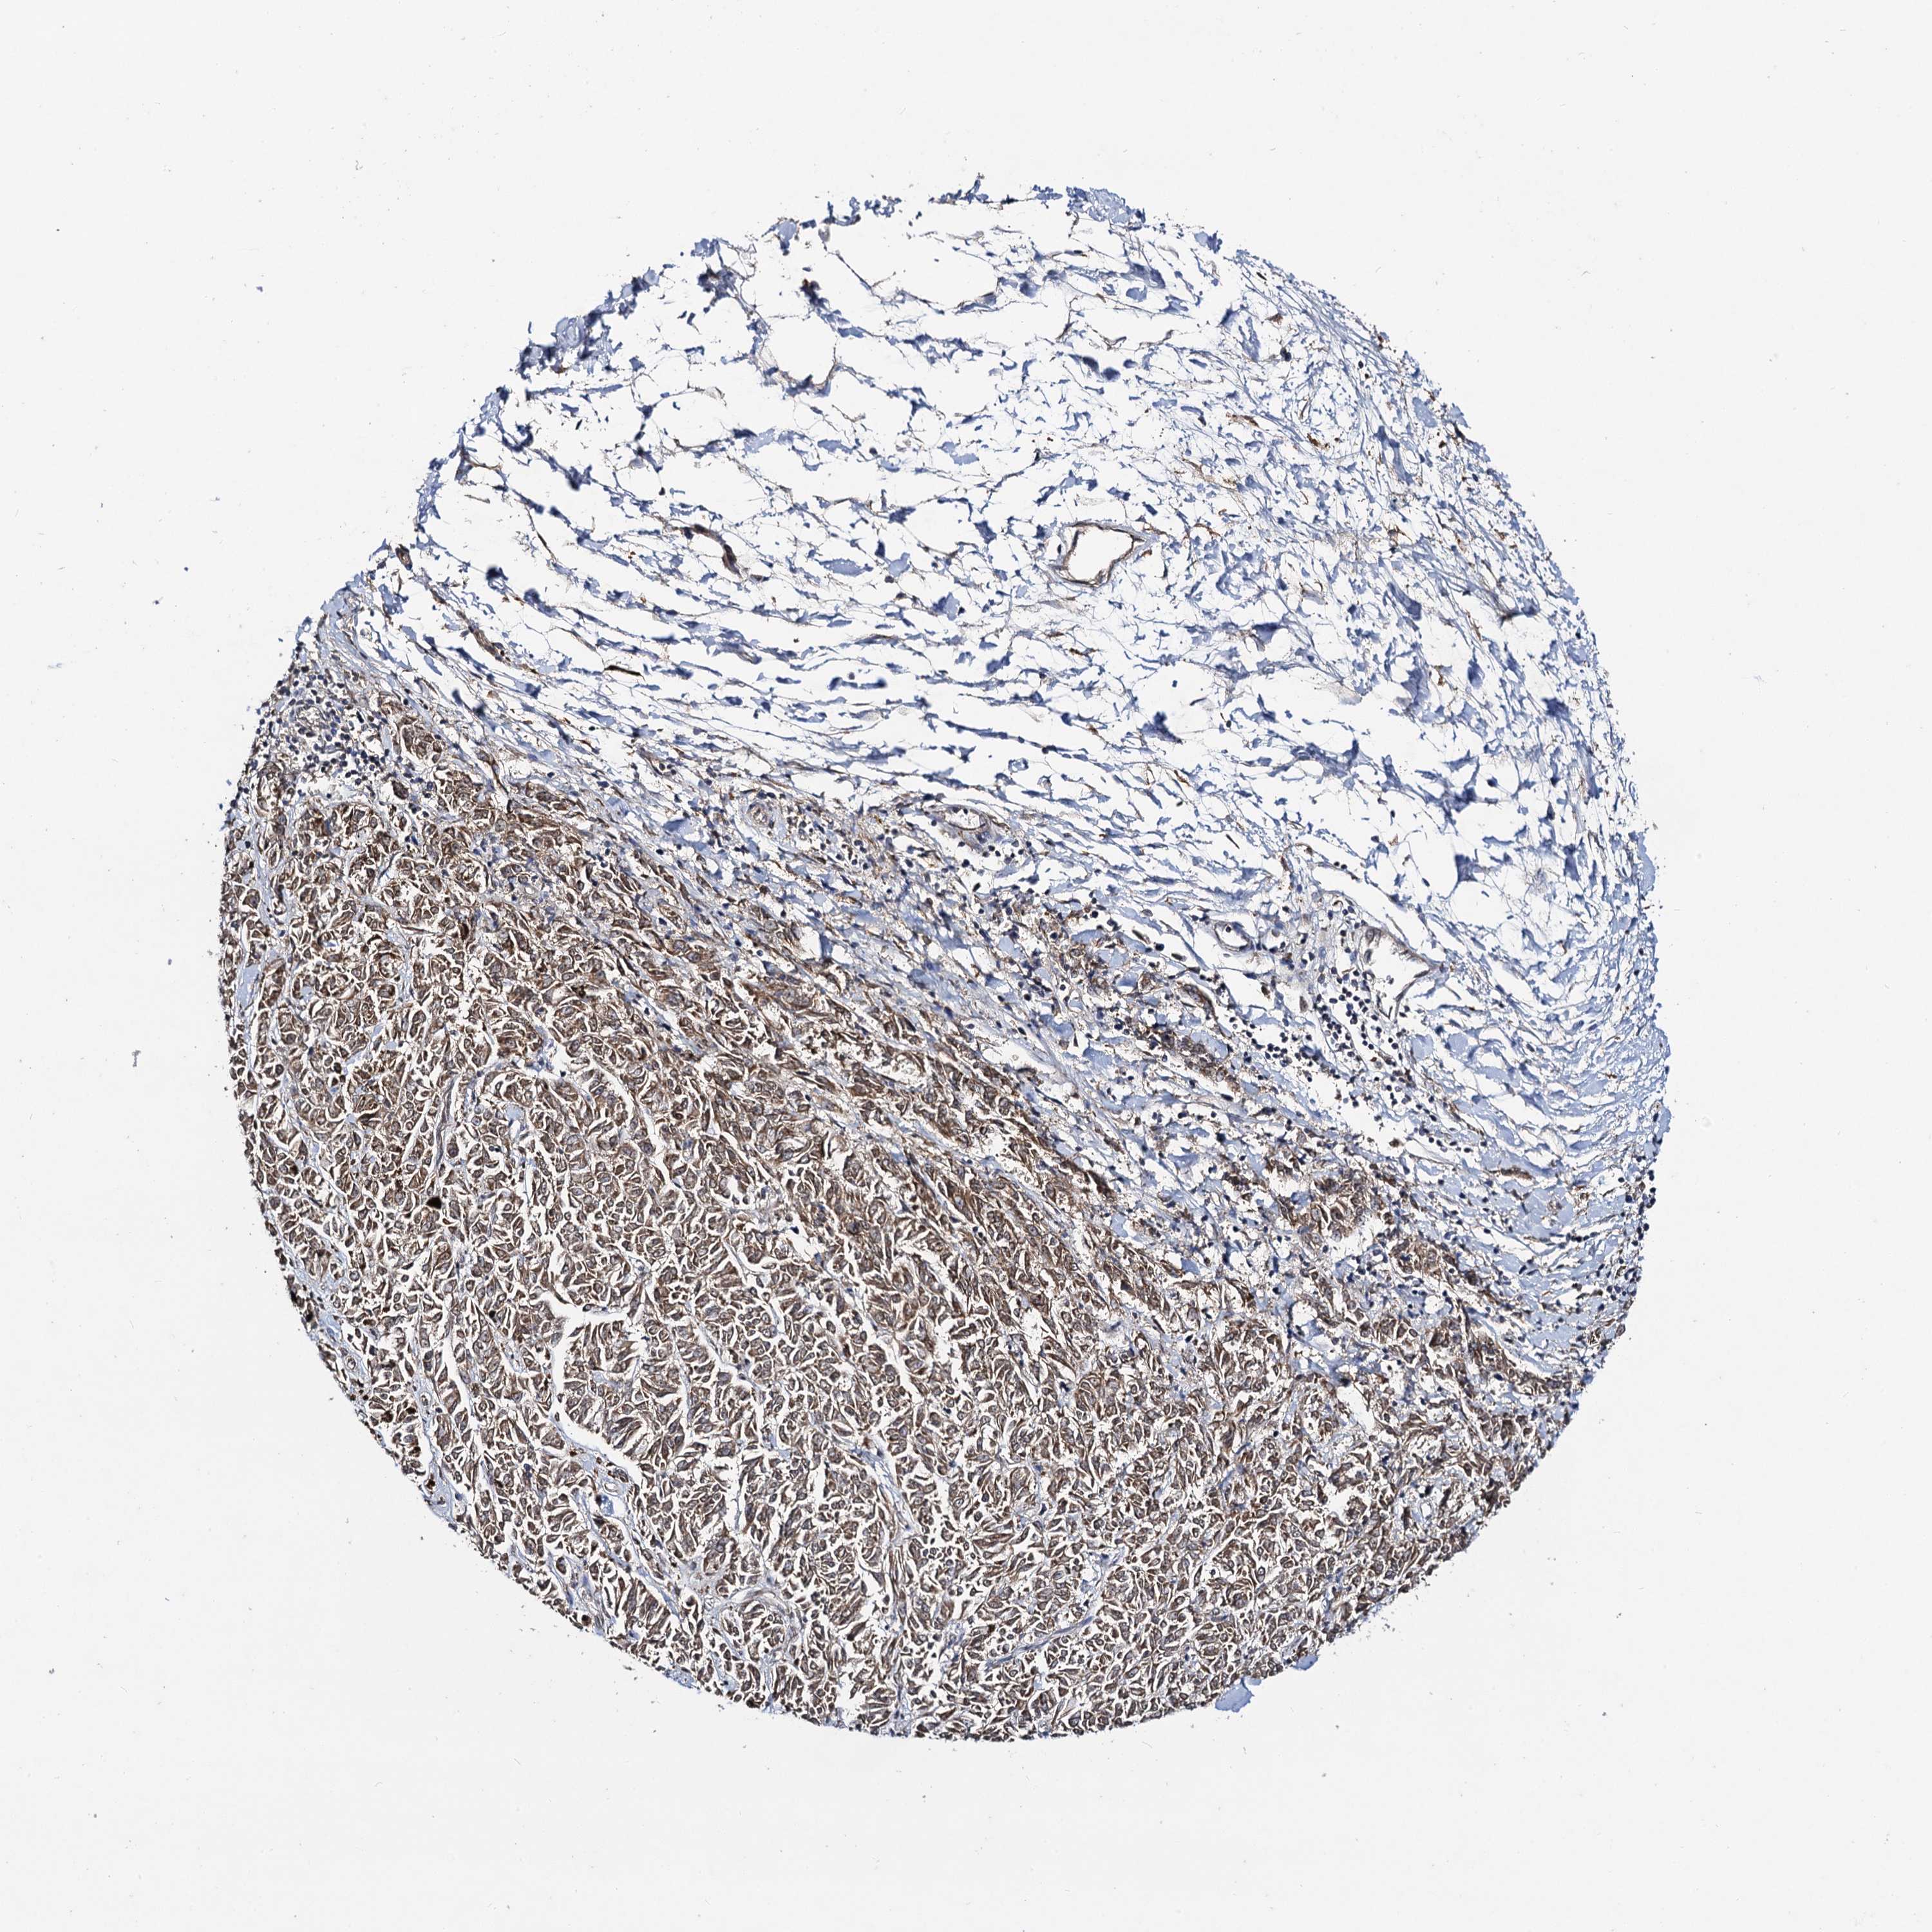

MELANOMA - Protein expressioni

A mouse-over function shows sample information and annotation data. Click on an image to view it in a full screen mode. Samples can be filtered based on level of antibody staining by selecting one or several of the following categories: high, medium, low and not detected. The assay and annotation is described here.

Note that samples used for immunohistochemistry by the Human Protein Atlas do not correspond to samples in the TCGA dataset.

Antibody stainingi

Antibody staining in the annotated cell types in the current human tissue is reported as not detected, low, medium, or high, based on conventional immunohistochemistry profiling in selected tissues. This score is based on the combination of the staining intensity and fraction of stained cells.

Each image is clickable and will lead to virtual microscopy that enables deeper exploration of all samples and also displays staining intensity scores, fraction scores and subcellular localization as well as patient and tissue information for each sample.

Antibody HPA040978

Staining

High

Medium

Low

Not detected

Intensity

Strong

Moderate

Weak

Negative

Quantity

>75%

75%-25%

<25%

None

Location

Nuclear

Cytoplasmic/membranous

Cytoplasmic/membranous,nuclear

Malignant melanoma, NOS

Malignant melanoma, Metastatic site